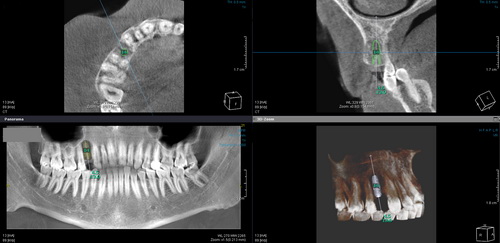

Fogászati CT (CBCT)

A panoráma-röntgen 2 dimenziós képalkotásához képest a fogászati CT 3 dimenziós képalkotása tizedmilliméter pontossággal ábrázolja az állkapcsokat, a bennük elhelyezkedő fogak helyzetét. Ezáltal olyan plusz információkhoz juthatunk (milyen vastag és milyen sűrűségű az állcsont csontszerkezete, környező anatómiai képletek), amelyek szájsebészeti beavatkozások sikeres elvégzéséhez nélkülözhetetlenek.

Hagyományos fogpótlási eljárások (híd, korona) előtt is érdemes elvégeztetni e precíz képalkotói vizsgálatot, hiszen egy fogágybetegségtől

(parodontosis) meggyengített (ám a hagyományos röntgennel nem teljesen megítélhető állapotú) fogra felhelyezett híd csak rövid ideig képes ellátni funkcióját, a fogmű hamarosan cserére szorulhat.

Ezen kívül egy bonyolultnak ígérkező bölcsességfog eltávolítása előtt (az arcüreg közelsége, közelben futó ideg érintettsége) is ajánlott a kezelés minél szövődmény mentesebb, a lehető legkevesebb kellemetlenséggel történő elvégzéséhez.